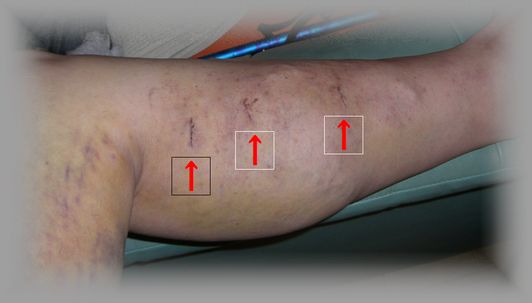

静脈のあとと内出血が痛い・・・静脈瘤の治療

内出血した部分が痛い・・

静脈瘤の手術をして早くも一週間

この間痛み止めを飲み続けた

メスを入れた傷跡は痛くないのですが・・・・ストリッピング術で助脈を抜き去ったあとが・・

内出血し、かつ引き抜くため、肉や神経にも影響を与えているらしく・・痛いのである

特に、歩くときには・・・ズキン!ズキン!と・・・ううううう~ たまない

そのため、どうしても足を引きずるような歩き方になってしまい弁慶の泣き所と言われている前頸骨筋がパンパンに張って歩けないほどになる

これにはさすがに参りました(^_^

一昨日の夜など、痛くって歩けなくて、妻の松葉杖を借りてトイレに・・・

でも足を高くして、痛み止めを飲んで寝ていると、朝には何とかむくみと痛みが和らいだので出勤した

今日は検診

手術のあとを初めて目の当たりにした。

左右ともそけい部のほか4カ所にメスが入ったようであるが、傷跡は順調に回復しつつあるようだ。

醜い足だが写真をアップしますね。

<右足の傷のうち3カ所>

<左足の傷のうち2カ所>